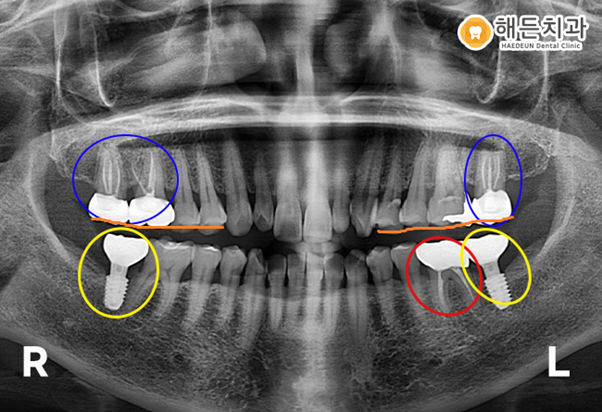

그런데 파란색 동그라미의 위의 양쪽 최후방 어금니들을 보시면 치아가 밑으로 쳐져 내려와

옆에 치아들과 높이가 다른 것을 보실 수 있습니다.

맞물리는 치아가 상실된 후 오랫동안 방치한 경우, 치아들이 솟구치거나 내려 앉게 되는 정출이 발생하게 됩니다.

위 상황에서 양쪽 아래에 임플란트를 진행하게 되면,

맞닿는 치아의 정출로 인해 추후 임플란트 머리를 올리는 작업을 하기 어렵습니다.

그래서 정출이 되어 내려앉은 치아들을 옆 치아들과 같은 높이를 맞추기 위해

신경치료 및 치아 삭제를 통한 크라운 치료가 필요합니다.

천안아산치과 해든치과에서 치료를 받은 후 사진입니다.

양측 아래 최후방 어금니자리에 임플란트 치료를 완료하였고,

충치가 있던 왼쪽 아래 어금니는 신경치료 및 크라운 치료를 완료하였습니다.

그리고 위의 정출된 치아들을 옆에 치아들과 높이를 맞추며, 신경치료 및 크라운치료를 진행했습니다.